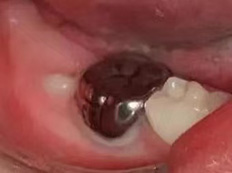

龋齿充填后注意事项

6、后牙龋坏缺损较大或龋坏位置不容易充填固位,患牙充填体反复脱落,建议行预成冠修复;